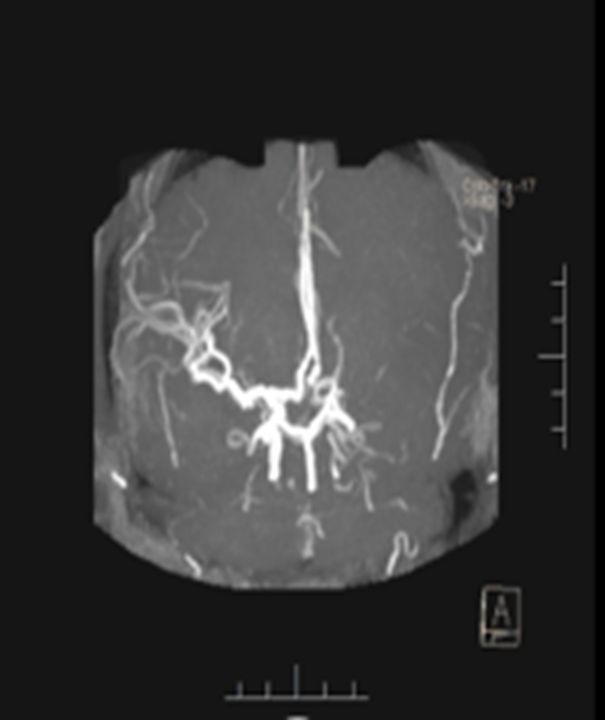

影像诊断

病历夹什么径技·第151期|串联营病历夹:京广连营_https://www.jmylbn.com_新闻资讯_第72张

病历夹什么径技·第151期|串联营病历夹:京广连营_https://www.jmylbn.com_新闻资讯_第73张

病历夹什么径技·第151期|串联营病历夹:京广连营_https://www.jmylbn.com_新闻资讯_第74张

<<滑动查看下一张图片>>

结论:颅脑CT提示左侧基底节、放射冠区腔隙样软化灶。颅脑DWI提示双侧小脑、桥脑、中脑、双侧海马、双侧枕叶、右侧丘脑及右侧胼胝体多发急性脑梗塞。颅脑MRA提示基底动脉及双侧大脑后动脉未见显示;右侧大脑中动脉中-重度狭窄;脑动脉硬化。初步诊断为急性后循环脑梗死,基底动脉闭塞。